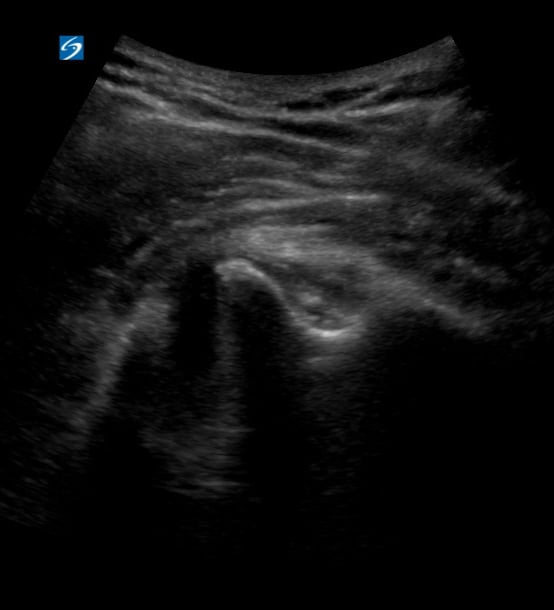

A hematoma, in musculoskeletal (MSK) ultrasound, is a localized collection of blood outside of blood vessels, often resulting from trauma, surgery, or underlying conditions. Appearing as a fluid collection on ultrasound, its characteristics vary based on age—from anechoic (fresh) to hyperechoic/heterogeneous (clotted/organizing). MSK ultrasound is crucial for diagnosing, characterizing, and monitoring hematomas, differentiating them from other masses, and guiding interventions.

Accurate ultrasound assessment of MSK hematomas helps clinicians determine size, location, and potential complications like nerve compression or infection. Early identification through medical ultrasound facilitates timely management, improves patient outcomes, and prevents chronic issues, making precise imaging vital for musculoskeletal care.